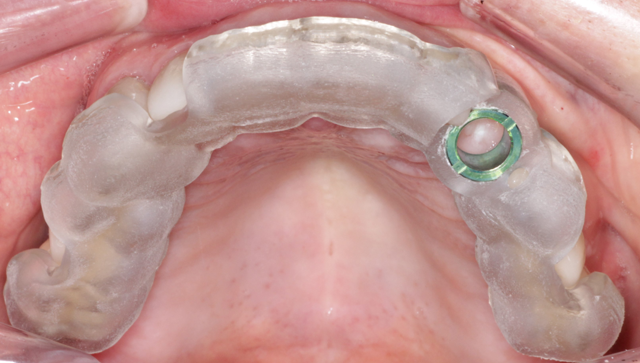

The patient was taken to the oral surgicenter where, under intravenous sedation, the maxillary left canine was surgically removed using appropriate periotomes and elevators. The tooth-borne surgical guide was placed (Fig. 8) and, using the Biohorizons Guided Surgical protocol, the Biohorizons Tapered Internal 4.6mm x12mm immediate implant was placed (Fig. 9). Ostell reading of 68 confirmed sufficient initial stability to provide an immediate load.

Fig. 7 Fig. 8